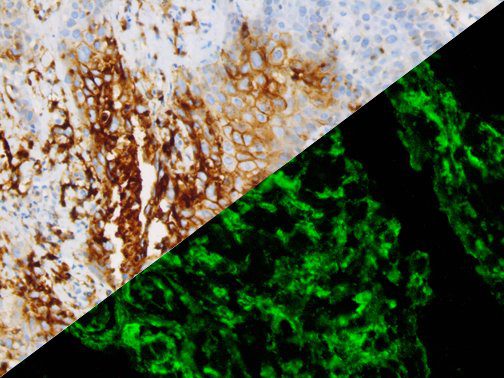

It is the ICU physician who is most likely to witness one of the deadliest manifestations of the abnormal immunological response, the cytokine storm syndrome (CSS). This response is also referred to by some as the cytokine release syndrome (CRS). CSS is characterized by continuous activation and expansion of macrophage and lymphocyte populations, which secrete large amounts of cytokines, causing the cytokine storm. This massive cytokine release is akin to hemophagocytic lymphohistiocytosis (HLH) disease, a syndrome characterized by initial unchecked and persistent activation of cytotoxic T lymphocytes and NK cells.

Clinical and laboratory manifestations of HLH include fever, enlarged liver and/or spleen, neurologic dysfunction, coagulopathy, liver dysfunction, cytopenias (i.e., low levels of erythrocytes, leukocytes, and/or platelets), hypertriglyceridemia, hyperferritinemia, hemophagocytosis, and eventually diminished NK cell activity as the immune system becomes progressively paralyzed. HLH can be familial (primary HLH) or secondary to another disease process (sHLH), such as rheumatic disease, in which it is referred to as macrophage activation syndrome (MAS, characterized by elevated ferritin).